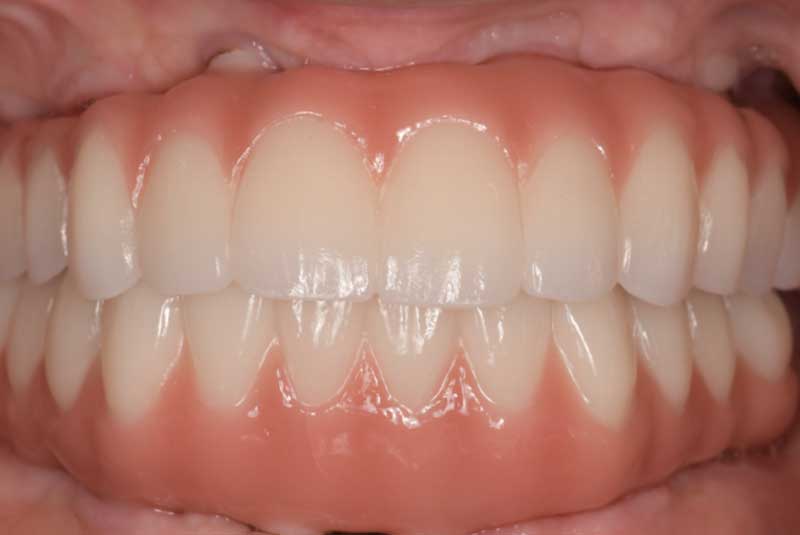

All on 6: Facial cut back (PFZ) Zirconia Full arch prosthesis for Maxilla and Mandible Before & After

The patient had her implants placed 20 years ago. Four implants, particularly in the maxilla, were not positioned ideally for me to utilize and restore, while the four implants in the mandible were outdated and no longer functional. The patient's primary concern is to restore both function and aesthetics.